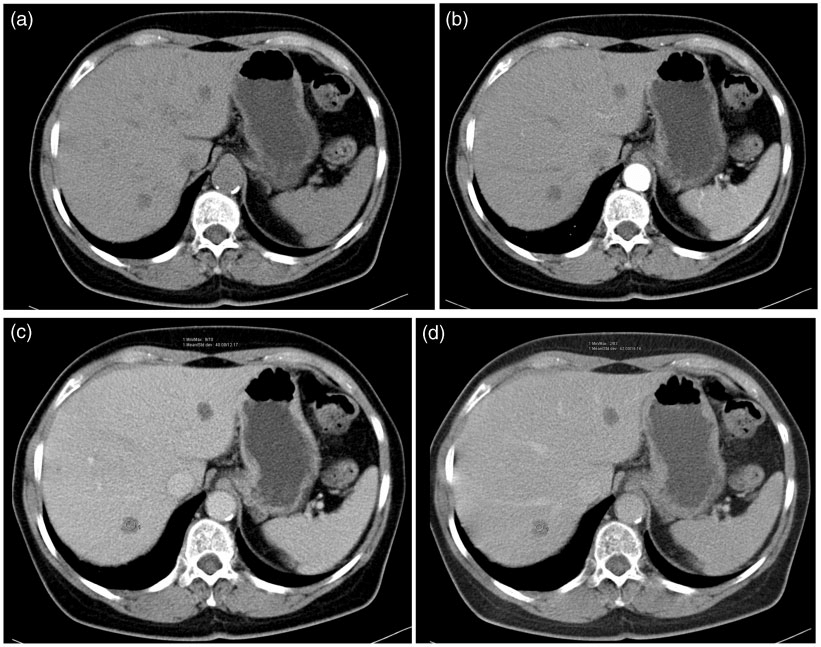

3.5 Types of CT Scans and Phases

CT scans are classified based on their applications and imaging phases as shown in Fig.4:

• Non-Contrast CT: This imaging modality, performed without the administration of a contrast agent, is commonly employed as an initial diagnostic tool for evaluating conditions such as fractures, hemorrhages, and neoplasms [14]. It provides essential baseline data regarding tissue density and structural integrity.

• Contrast-Enhanced CT: This scan has an iodine-based contrast agent administered intravenously or orally to enhance the visibility of vascular structures and organs [14]. It is essential in oncological assessments, abdominal imaging, and vascular studies. Following are the phases of Contrast-Enhanced CT:

• Arterial Phase: Images are acquired 25-30 seconds after contrast injection, ensuring enhanced visualization of arterial vessels and hypervascular lesions due to their increased contrast enhancement during this phase.

• Venous Phase: Images are acquired 60-90 seconds post-injection, this phase focuses on venous structures and provides valuable information about tumor perfusion and vascular integrity.

• Delayed Phase: Captured 10-15 minutes after contrast administration, this phase assesses the distribution of contrast within tissues, particularly beneficial for evaluating renal function and identifying tumors with varying vascularity.

Refer to caption

Figure 4: Liver CT scan taken from [44]. Fig. 4(a) Non-Contrast CT, 4(b) Contrast Enchanced CT - Arterial Phase, 4(c) Venous Phase, 4(d) Delayed Phase